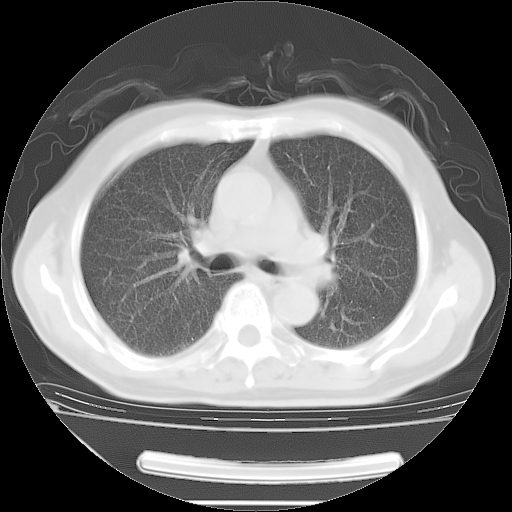

今天复查肺部CT,发现双肺广泛磨玻璃样改变。所以我把3月19日和5月9日相隔50天的肺部CT上传。请大家会诊。

2009年3月19日肺部CT片。

2009年3月19日肺部CT

5月9日肺部CT(在4月27日齐鲁医院肺部CT描述部分肺组织磨玻璃样改变,12天后肺组织广泛磨玻璃样改变)

大致读了系列胸部CT:纵隔窗无明显异常,肺窗:从4、27至今:主要是双肺中下野外带可见毛玻璃样改变,目前处于急性肺泡炎阶段,至于原因考虑1、结替组织或胶原血管性疾病所致?2、恶性疾病如恶组在肺部所致的表现或细支气管肺泡癌?3、药物或其它原因如肺蛋白沉着症所致肺泡炎目前不太可能?总之,明天就去请我院的呼吸科、感染科、血液科和临免专家会诊哈。